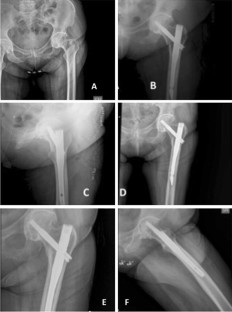

Fig. 1